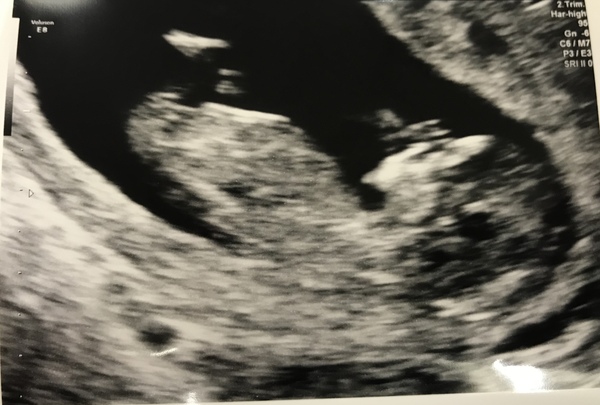

A very wriggly baby seen today! Good to know the drop in symptoms means nothing at all. Very relieved. Now to get to the 16 week scan and we can start telling people

Beautiful scan @mynameismrg!! Are you getting agender scan at 16weeks?

mynameisMrG · 25/06/2019 16:33

Thank you @megganonion, no not a gender scan, I get scanned every four weeks. I lost two babies at 15 weeks last year so 16 weeks is our safety scan😊

Aw @mynameisMrG that pic made me smile Smile

Awww such a lovely scan and I am sure it was lovely to see so much movement too - now you can enjoy the lack of symptoms!!

@mynameisMrG your scan picture has disappeared! I saw it earlier though! Glad all went well!

mynameisMrG · 25/06/2019 20:25

That sounds positive @primarywoodle

I took it down @DaisyMay25 as I realised it had all my details on the top still🤦🏻‍♀️ Here it is with the top cropped